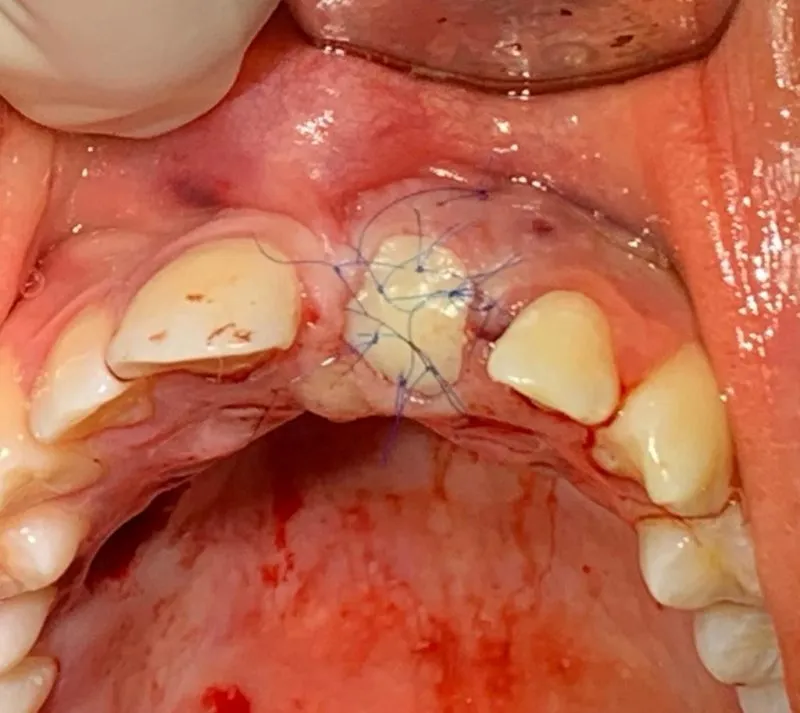

Po wyrwaniu zęba, dziąsło przechodzi przez różne etapy gojenia, które mogą być zaskakujące dla pacjentów. Na początku, dziąsło może być opuchnięte, zaczerwienione i bolesne, co jest normalną reakcją organizmu na zabieg. W zębodole tworzy się skrzep, który stanowi naturalny opatrunek, chroniący ranę przed infekcją. Skrzep ma ciemnoczerwoną barwę i gładką strukturę, co jest oznaką, że proces gojenia się rozpoczął.

Po zabiegu ekstrakcji zęba, normalne objawy obejmują lekkie opuchnięcie i zaczerwienienie w okolicy dziąsła. W ciągu pierwszych kilku dni pacjenci mogą odczuwać ból, który zazwyczaj jest łagodny i ustępuje wraz z czasem. Zmiany w kolorze dziąsła, takie jak ciemnoczerwony skrzep, są również normalne i wskazują na to, że rana jest zabezpieczona. W miarę postępu gojenia, skrzep bieleje, co oznacza, że proces regeneracji tkanki jest na dobrej drodze.

Gojenie dziąseł po wyrwaniu zęba to złożony proces, który przebiega w kilku etapach. Po pierwsze, tuż po zabiegu, w zębodole tworzy się skrzeplina, która działa jak naturalny opatrunek. Skrzeplina jest kluczowa, ponieważ chroni ranę przed zanieczyszczeniem i infekcją. W ciągu pierwszych kilku dni, dziąsło może być opuchnięte i zaczerwienione, co jest normalną reakcją organizmu na zabieg.